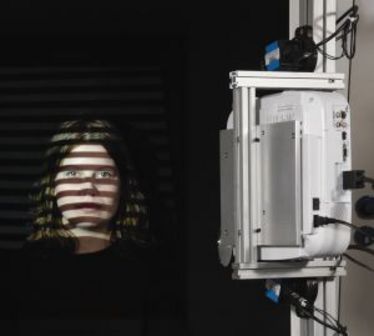

Deutsch-Chinesisches DFG-Projekt

Deutsch-Chinesisches DFG-Projekt